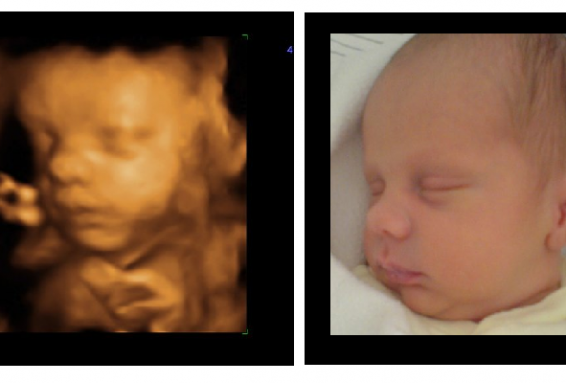

3d Ultrasound Of Baby And Newborn Stock Photo C Dementevajulia

3d Pregnancy Ultrasound And Newborn Baby Stock Image C001 7115

Baby Scan Picture Compared With Picture Of Baby Born 3d 4d

3d Pregnancy Ultrasound And Newborn Baby Stock Image C001 7116